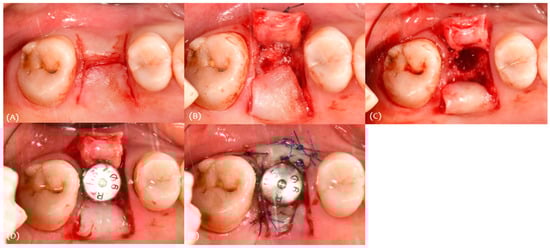

3.1. Case 1

2.2. Surgical Protocol